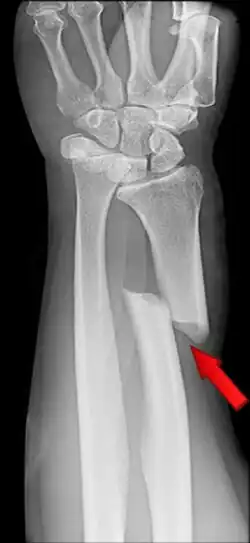

Fracturas

Se entiende por fractura una solución de continuidad en algún punto del hueso. Generalmente está causada por un traumatismo que provoca una tensión que supera la resistencia del hueso, causando su rotura. Tienen tendencia a consolidar gracias a los mecanismos naturales de autorregeneración que se inician con la formación de un callo de fractura. En muchas ocasiones el tratamiento consiste en realizar una inmovilización del área mediante vendaje de yeso para facilitar la curación natural y evitar el desplazamiento de los fragmentos.